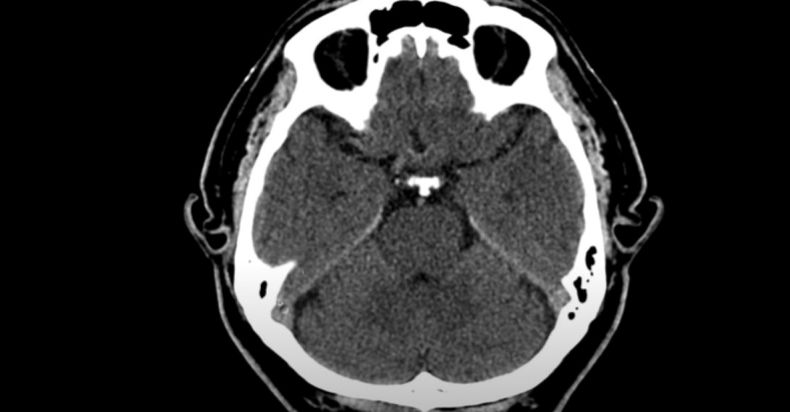

Detalló que el infarto cerebral, también conocido como enfermedad cerebral vascular o embolia, sucede cuando se forma un coágulo en alguna arteria del cerebro, lo que implica que la arteria se obstruya, no haya flujo sanguíneo y con ello, falta de oxigenación.